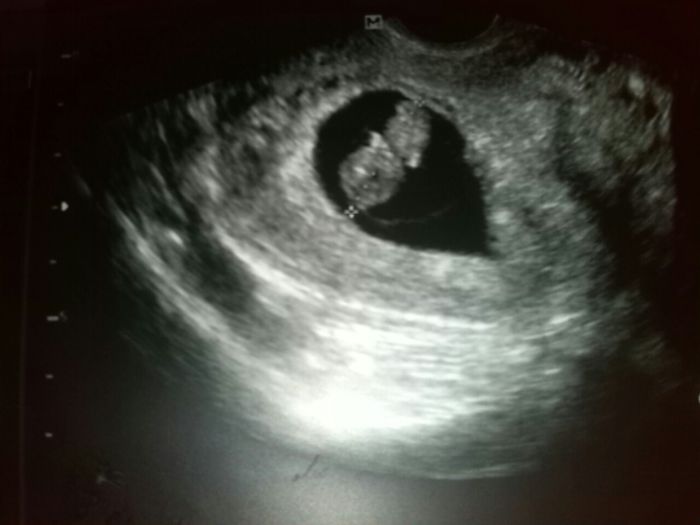

jeeee ten je krásnej, já mám takovýho medvíka ..medvědici

jee hezky! a i fotka se povedla :))